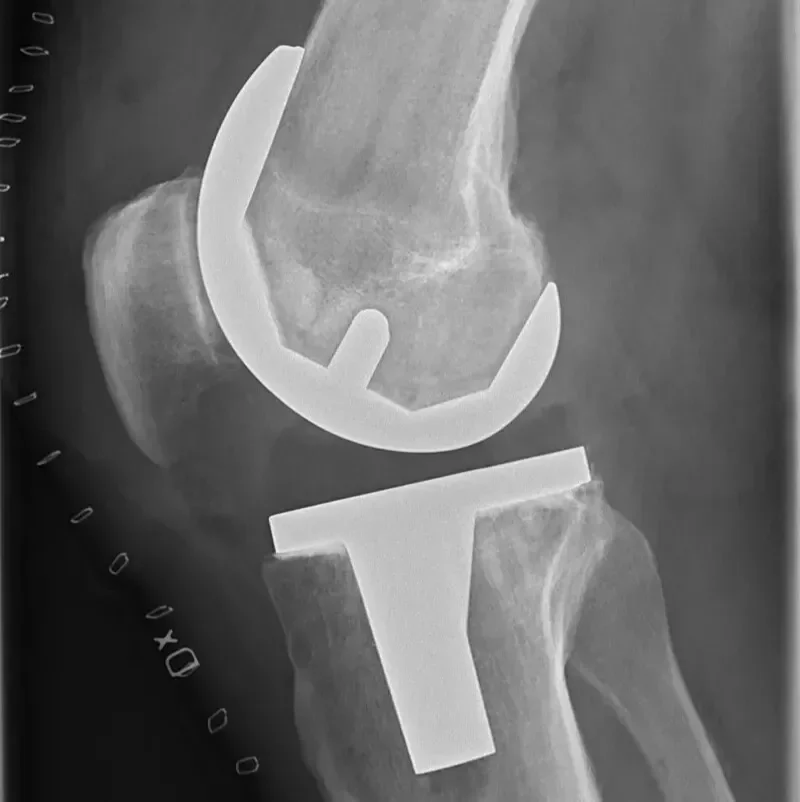

Endoproteza kolena

Endoproteza kolena je umetni sklep, s katerim kirurg med operacijo nadomesti prizadete dele kolena.

Navodila po endoprotezi kolena

Pomembna navodila za paciente po vstavitvi endoproteze kolena za varno in hitro okrevanje.